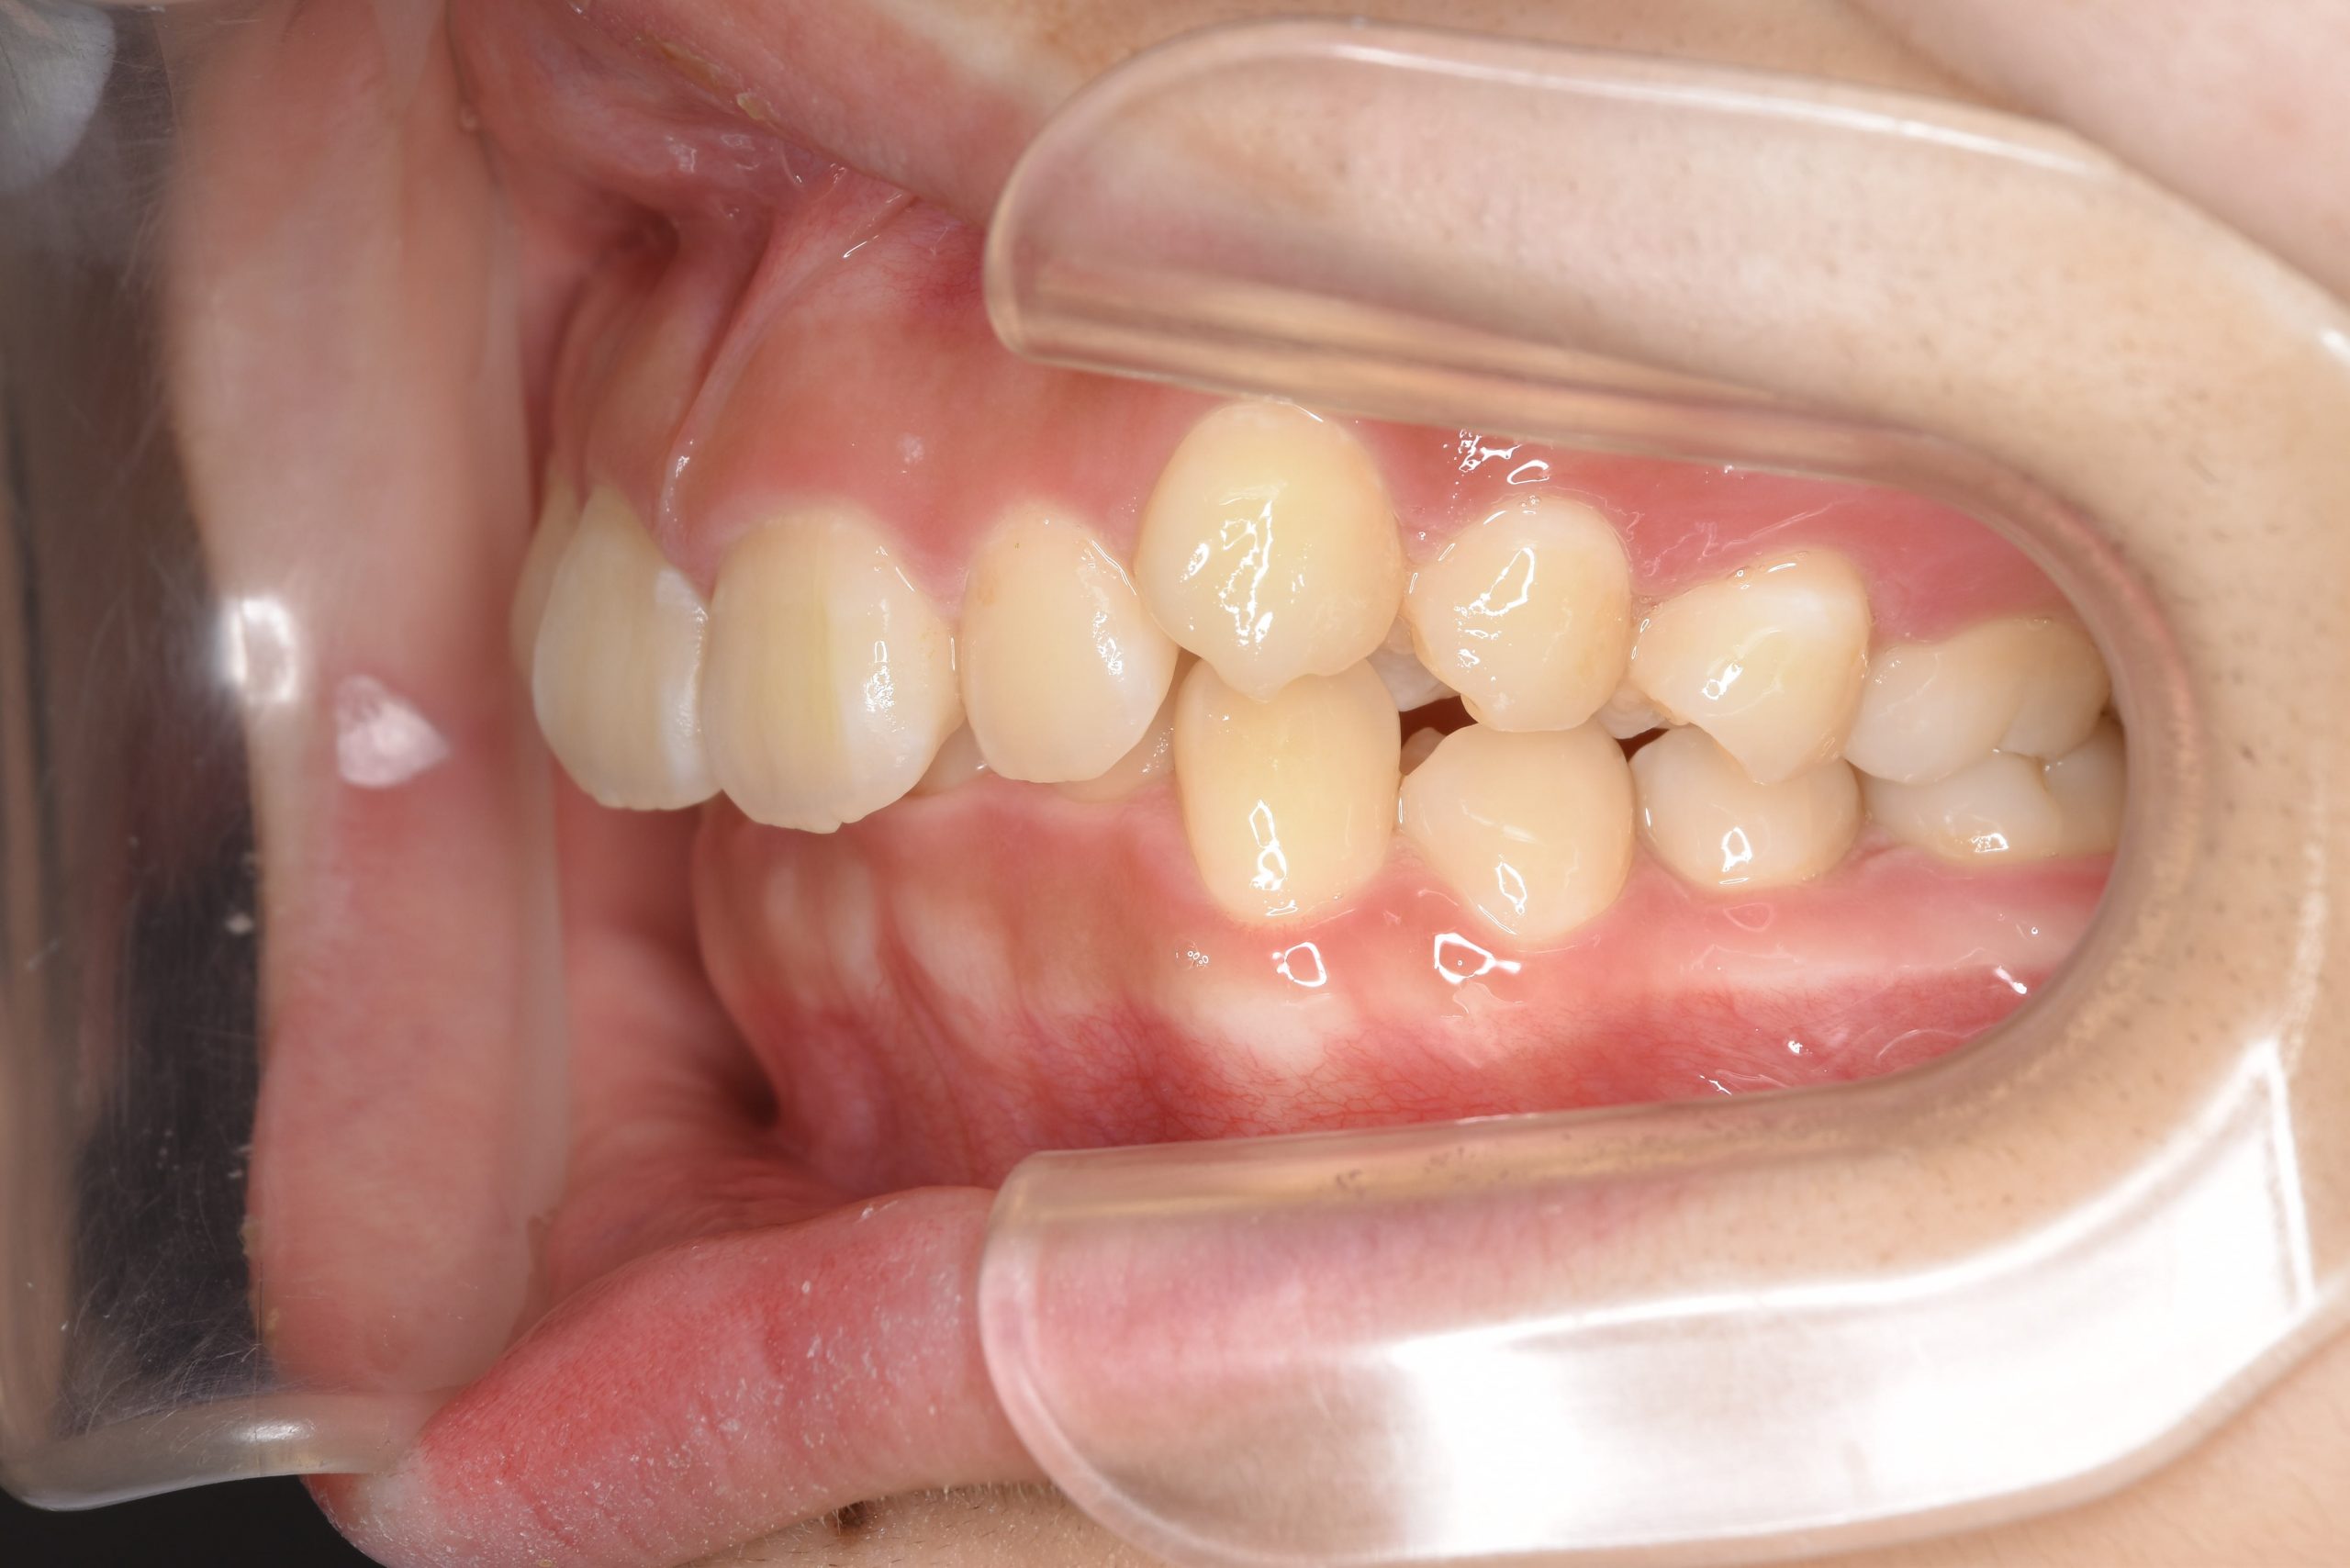

アフター

ワイヤー矯正治療|症例_349

施術内容 MSEと下顎リンガルアーチを用いて上下顎骨を拡大した。

その後マルチブラケット装置を用いて非抜歯で歯牙を配列し、良好な咬合を獲得した。

治癒期間 3年7か月間